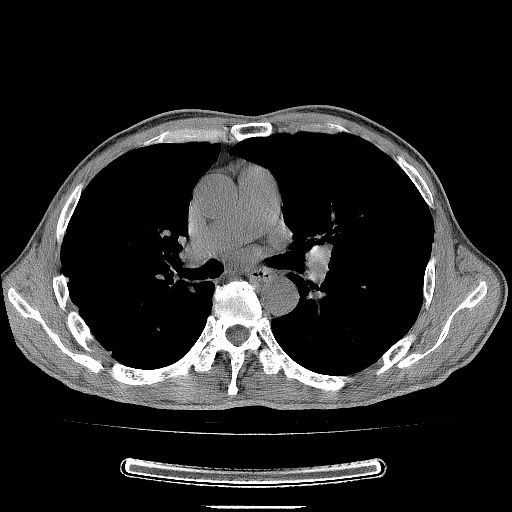

男性患者,63岁。右侧胸背部疼痛2月,加重一周。

考虑:右肺中央型肺癌并右肺下叶不张;两肺尖继发性肺结核。

右肺下叶支气管狭窄闭塞,右下肺不张,气管前间隙淋巴结肿大,两上肺散在分部粟粒灶,沿肺血管支气管束分部,血管支气管束走形较为光滑。考虑右肺中心型肺癌合并肺不张,纵隔淋巴结转移,两上肺癌性淋巴管炎

右肺下叶中心性肺癌并纵隔淋巴结转移,左侧肋骨转移。双肺上叶继发性结核表现。

1)右肺下叶中心性肺癌并纵隔淋巴结转移,两肺转移,左侧肋骨转移。2)双肺上叶继发性结核。

右肺下叶中心性肺癌并纵隔淋巴结及两肺、左侧肋骨转移。双肺上叶继发性结核表现。